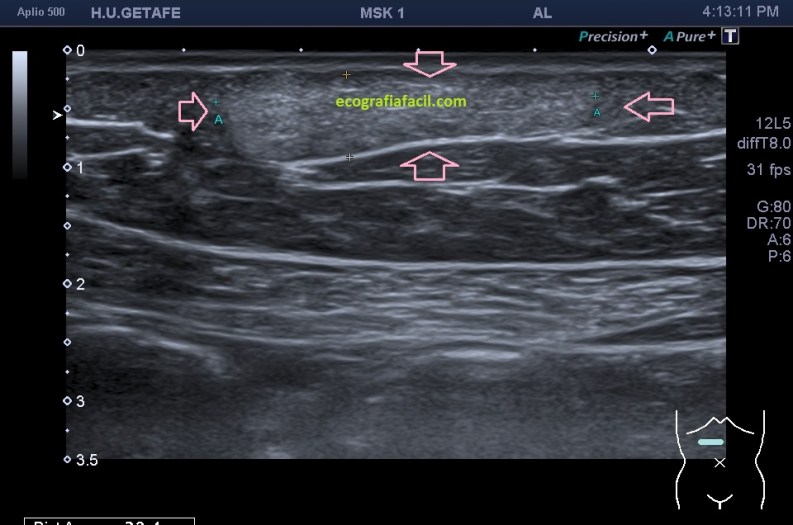

Normalmente encontraremos una lesión bien definida, hiperecogénica o isoecogénica con los márgenes definidos, en ocasiones lobulados, pero casi siempre ovalados con su eje largo paralelo a la piel en el plano subcutáneo y sin vascularización. Así, mira:

La estructura que estamos estudiando en este Caso 1, en las imágenes 1 a 6, es el estudio de protocolo de cualquier lesión, localización (flechas rosas), medición, vascularización. La 7 te marca una situación habitual en el estudio de los lipomas, y es que la paciente se nota un bulto, pero en la misma exploración descubrimos más, como es la pequeña lesión hiperecogénica que está justo al lado de la lesión mayor y palpable. Algunos de ellos, repito, pueden ser imperceptibles para la paciente, como era este caso. La imagen 8 es otra lesión próxima que sí era palpable.

En este caso las lesiones son todas hiperecogénicas comparativamente con el tejido hipoecogénico de la grasa del tejido celular subcutáneo. Son más o menos ovaladas, su eje largo es paralelo a la piel, no tienen vascularización y tienen medidas distintas. El diagnóstico final fue de lipomas. La paciente tenía más en la extremidades.

Cuidado, estas lesiones pueden presentarse hipoecogénicas, en ocasiones es complicado encontrarlos y es el reborde el que nos marca la posición de la lesión.